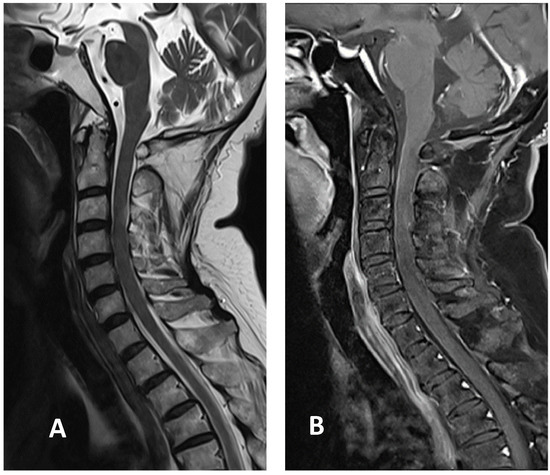

Based on the Brighton case definition for myelitis, the patient was diagnosed with LETM with level 2 diagnostic certainty [6]. Pulse therapy with intravenous methylprednisolone (1 g/day for five days) was initiated after admission. The patient showed improvement in limb and sacral paresthesia symptoms after the pulse therapy, following which, oral prednisolone (60 mg/day) was administered. The examinations also revealed a deficiency in vitamin B12 levels, at 131 pg/mL. Therefore, hydroxocobalamin (1 mg/day) was included in the regimen to compensate for the deficiency. Since the patient gradually regained sensation in the limbs affected by paresthesia, prednisolone was slowly tapered. Her gait also improved following rehabilitation. The patient was discharged two weeks after admission with oral prednisolone, 15 mg twice daily. It was tapered to 10 mg twice daily 1 week later during outpatient department treatment. A follow-up cervical MRI two weeks after discharge showed that the T2 hyperintensity had decreased in size, with minimal enhancement in the T1-weighted image (Figure 3). Prednisolone was tapered to 5 mg three times daily. It was further tapered to 10 mg once daily, four weeks after discharge. Her gait improved without the assistance of a cane.

Figure 3.

Cervical MRI images two weeks after discharge: (A) sagittal T2-weighted image showing the decreased size of hyperintensity in the cervical cord at the C3 level; (B) sagittal T1-weighted image with contrast showing minimal enhancement in the cervical cord at the C3 level.